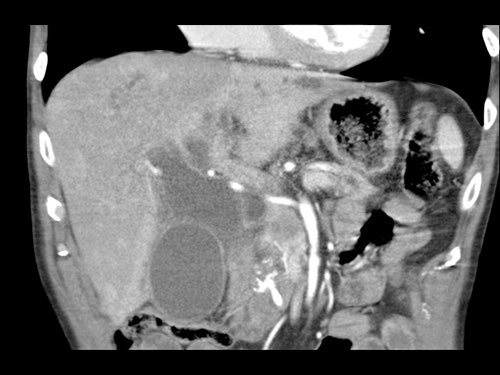

Ở những bệnh nhân dự kiến phẫu thuật tụy, điều quan trọng là cần đặc biệt chú ý tìm kiếm nguyên ủy bất thường của động mạch gan phải hoặc động mạch gan chung.

Các động mạch này xuất phát từ phía phải của động mạch mạc treo tràng trên (SMA) và đi qua vùng lân cận đầu tụy, làm tăng nguy cơ xâm lấn của khối u hoặc tổn thương do phẫu thuật.

Tần suất được ghi nhận của các bất thường đặc hiệu này lần lượt là 11-21% và 0,5-5%.

Các hình ảnh mặt phẳng đứng ngang của một bệnh nhân có khối u ở đầu tụy và động mạch gan phải phụ thêm.

Lưu ý sự áp sát của động mạch phụ thêm bởi khối u.